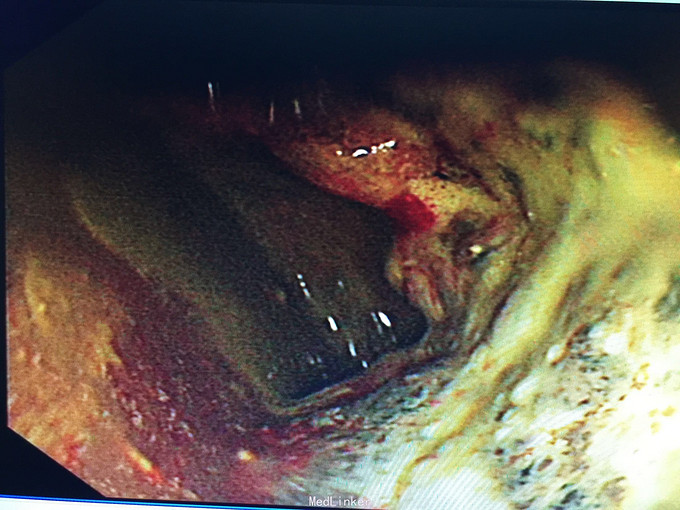

诊断:直肠癌, 预约结肠镜检查:距肛缘4cm见环肠肿物,凸凹不平,表面覆污秽苔,质硬,界不清。 病理结果为直肠腺癌。 病人回当地医院接受治疗。